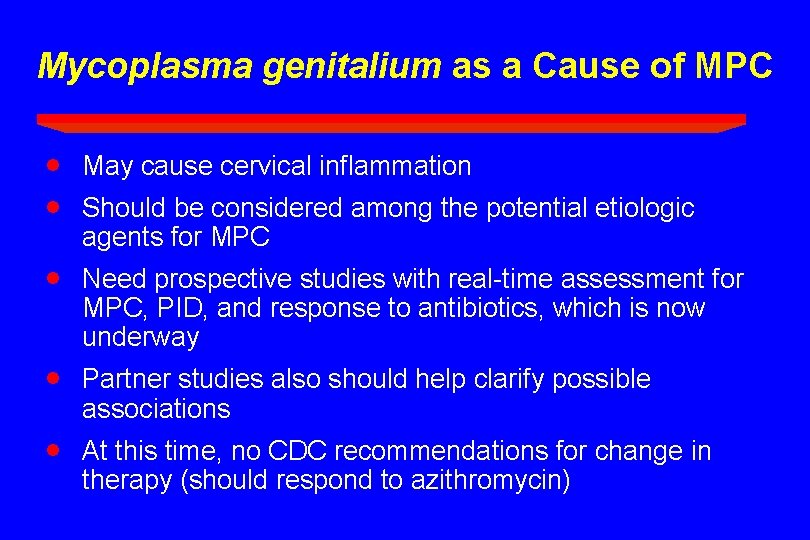

Mycoplasma genitalium as a Cause of MPC · · May cause cervical inflammation · Need prospective studies with real-time assessment for MPC, PID, and response to antibiotics, which is now underway · Partner studies also should help clarify possible associations · At this time, no CDC recommendations for change in therapy (should respond to azithromycin) Should be considered among the potential etiologic agents for MPC